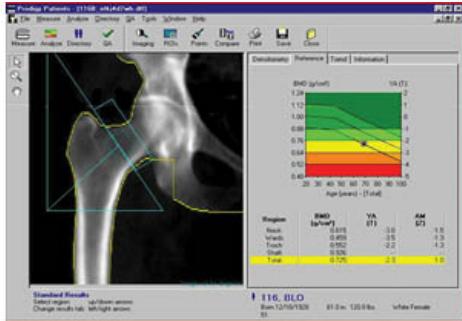

DEXA Scan

Overview

- Bone Mineral Density (BMD) measurement

- DEXA: Dual Energy X-ray Absorptiometry

- Primary sites: Spine / neck of femur

WHO Classification of BMD Using DEXA Scan

Reference: L2-L4 vertebrae

| Category | T-Score | Description |

|---|---|---|

| Normal | Within 1 SD of young adult mean | |

| Osteopenia | -1 to -2.5 | Between 1-2.5 SD below young adult mean |

| Osteoporosis | More than 2.5 SD below young adult mean | |

| Severe Osteoporosis | + fracture | Osteoporosis with history of fracture |

Note: T-score represents the number of standard deviations (SD) a patient is above or below the mean BMD of a young adult.